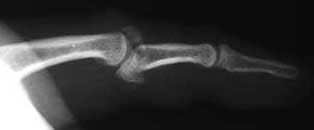

- Post-reduction the stability of the joint should be assessed and Elson's test5,6 performed to assess the central slip extensor mechanism. Any Boutonniere deformity which can be subtle should also be noted.

- In practice Elson's test is not always easy to perform or interpret. There is the traditional Elson's 5 and a modified version 6 which demonstrates the hyperextension of the DIPJ, as in in the left hand in (B).

- A Boutonnière deformity is the main concerning complication of a central slip tear/avulsion fracture

- The Boutonniere deformity sequence. (1) The PIP joint loses its dorsal extension force, so it starts to flex. (2) As the PIP flexes, the lateral bands slip volarly (below the axis of rotation of the PIP joint). (3) Once volar, the lateral bands act as flexors at the PIP joint rather than extensors—this locks in the deformity. Because the lateral bands are now tighter and pulled distally, they hyperextend the DIP joint. This results in flexion of the PIP joint with hyperextension of the DIP joint→ giving the characteristic “buttonhole” appearance — hence the name boutonnière (French for “buttonhole”).